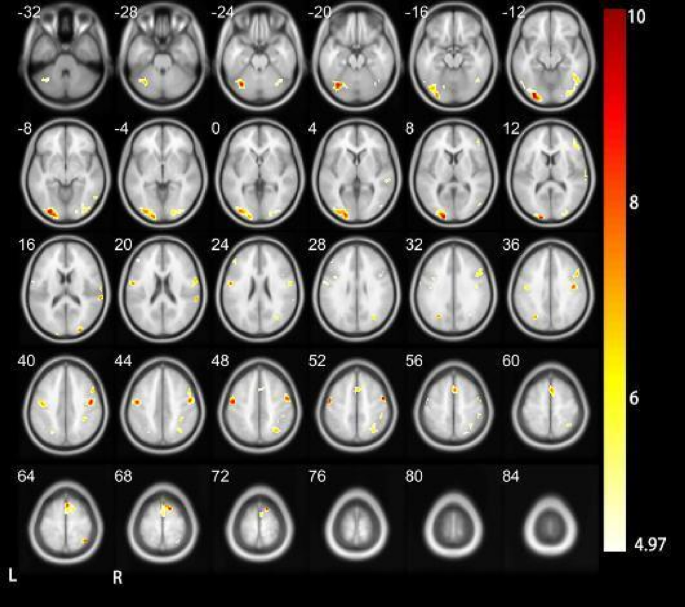

As shown in Tables 2 and 3; Figs. 2 and 3, when performing the Tone 1 task, the bilateral middle occipital gyrus brain area, right supplementary motor area brain area, bilateral precentral gyrus brain area and right parietal gyrus area of DC. The superior lobule brain area was activated; the bilateral middle occipital gyrus brain area and the left precentral gyrus brain area were activated in HC. The middle occipital gyrus is involved in visual processing. The supplementary motor area is responsible for motor planning and coordination. The precentral gyrus is related to motor control and voluntary movements, and the parietal gyrus is involved in multi-sensory information integration.

Compared with DC, no activation was found in the right supplementary motor area and right parietal lobule in HC. For the middle occipital gyrus and precentral gyrus, it was found that these brain areas were bilaterally active in DC. There was activation, while HC had activation in the bilateral middle occipital gyrus area and the left hemisphere precentral gyrus area.